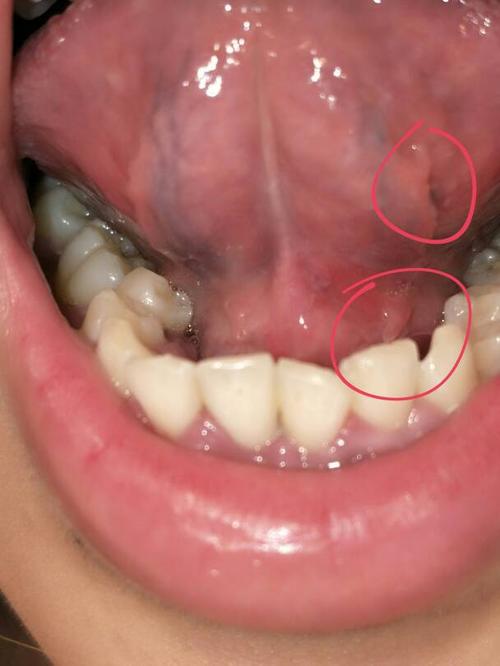

请医生帮我看下是尖锐湿疣吗,舌头下面和底部总共长了